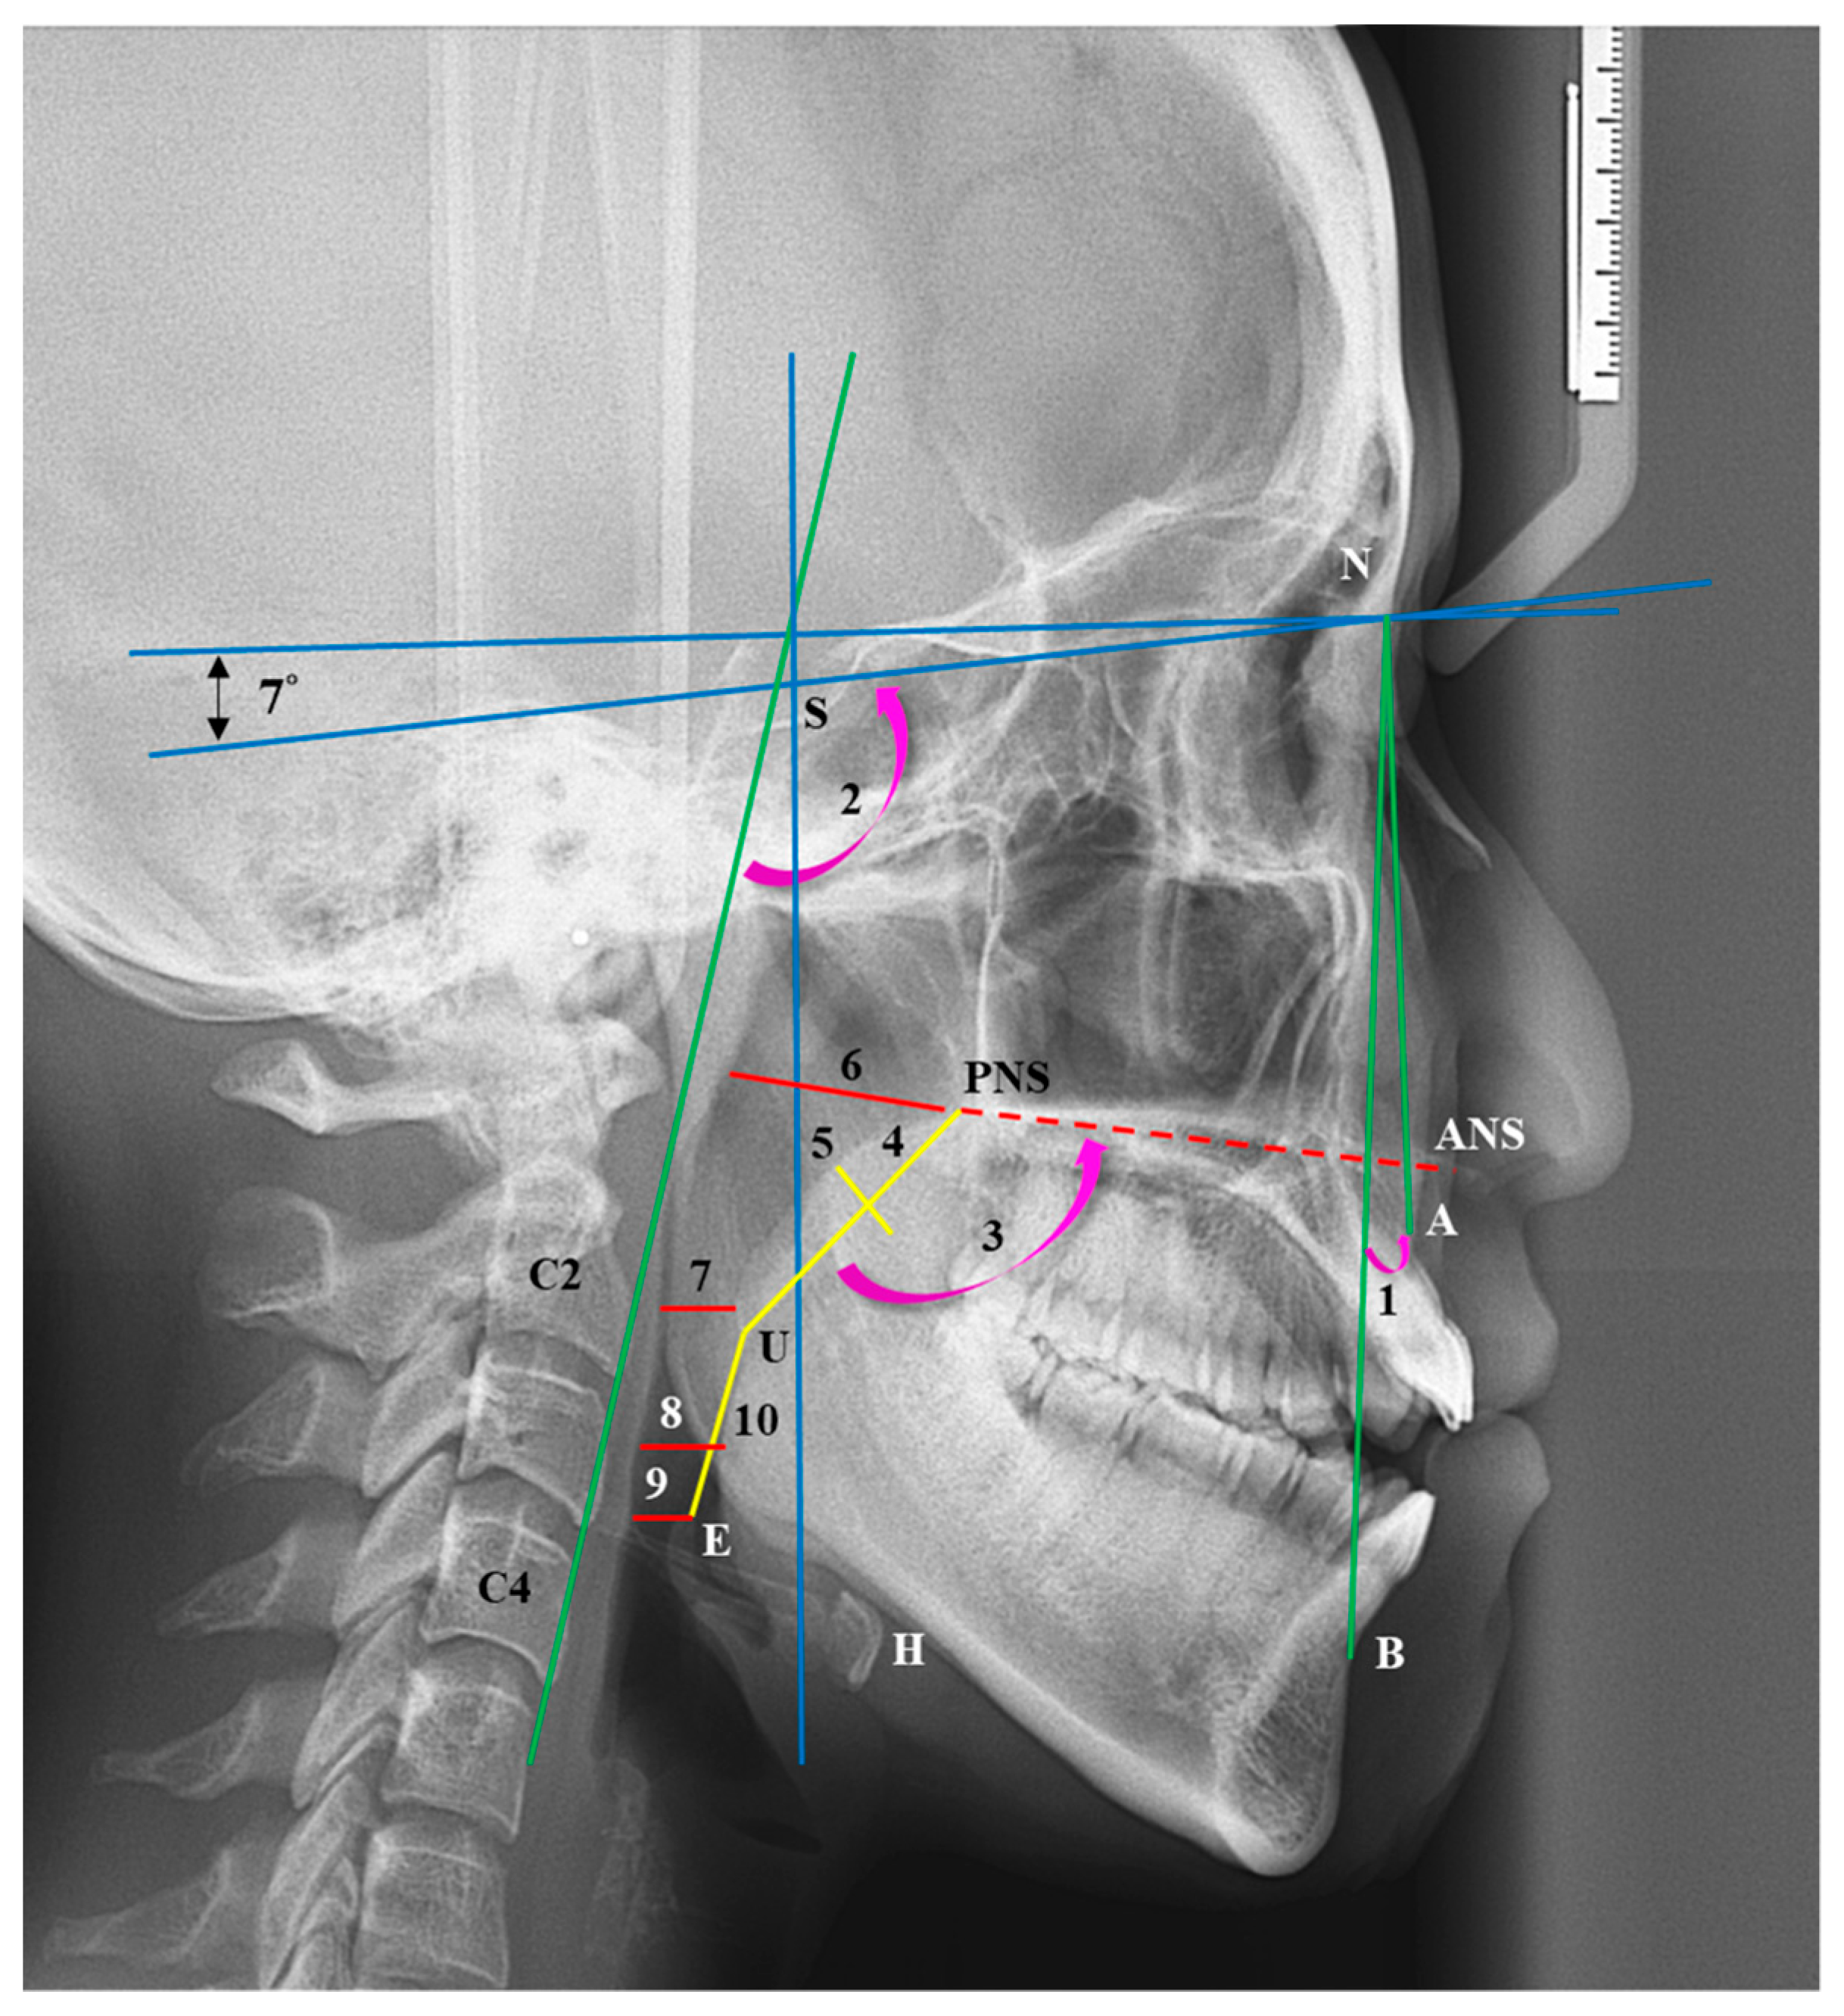

By using a 0.3 mm pencil, C.-M.C. manually identified cephalometric landmarks on tracing paper, as outlined in our previous study [8]. The cephalometric landmarks and angles are presented as follows (Figure 2):

• S: Sella (the midpoint of the pituitary fossa);

• N: Nasion (the most anterior point of the nasofrontal suture in the median plane);

• A: The most concave point on the anterior edge of the maxilla;

• B: The most concave point on the anterior edge of the mandibular symphysis;

• ANS: Anterior nasal spine (the most anterior and superior spine of the maxilla);

• PNS: Posterior nasal spine (the most posterior and superior spine of the maxilla);

• H: The most anterior and superior point of the hyoid bone;

• C2: The most anterior inferior point of the second cervical vertebra;

• C4: The most anterior inferior point of the fourth cervical vertebra;

• U: The lowest point of the uvula;

• E: The uppermost point of the epiglottis;

• ANB angle: The angle formed by point A, the nasion (N), and point B;

• Palatal angle: The internal angle between the length of the soft palate and the ANS–PNS line;

• C2C4-SN angle: The angle between the line passing through C2 to C4 and the SN line.

Reference lines were established with the X-axis set 7° upward of the line connecting S and N, and the Y-axis passing through S perpendicular to the X-axis.

The dimensions of the pharyngeal airway and soft palate are defined as follows:

• Nasal pharyngeal airway space (NPS): Extending from ANS and PNS to the posterior wall of the pharynx;

• Soft palate pharyngeal airway space (SPS): Shortest distance from the soft palate to the posterior pharyngeal wall;

• Tongue pharyngeal airway space (TPS): Shortest distance from the tongue to the posterior wall of the pharynx;

• Epiglottis pharyngeal airway space (EPS): Distance from the apex of the epiglottis to the posterior pharyngeal wall;

• Soft palate length (SPL): Length of the soft palate;

• Soft palate width (SPW): Width of the soft palate;

• UE length: Distance between U and E.

Figure 2. Cephalometric landmarks. S: sella; N: nasion; A point; B point; ANS: anterior nasal spine; PNS: posterior nasal spine; H: hyoid bone; C2: The most anterior inferior point of the second cervical vertebra; C4: The most anterior inferior point of the fourth cervical vertebra; U: uvula; E: epiglottis. Reference lines: The X axis in the X-rays was set as 7° upward of the line connecting the S and N, using N as the fulcrum. The line passing through S perpendicular to the X axis was considered to be the Y axis. Angular and linear measurements. 1: ANB angle; 2. C2C4-SN angle; 3: Palatal angle; 4: SPL (soft palate length); 5: SPW (soft palate width); 6: NPS (nasal pharyngeal airway space); 7: SPS (soft palate pharyngeal airway space); 8: TPS (Tongue pharyngeal airway space); 9: EPS (epiglottis pharyngeal airway space); 10: UE distance.